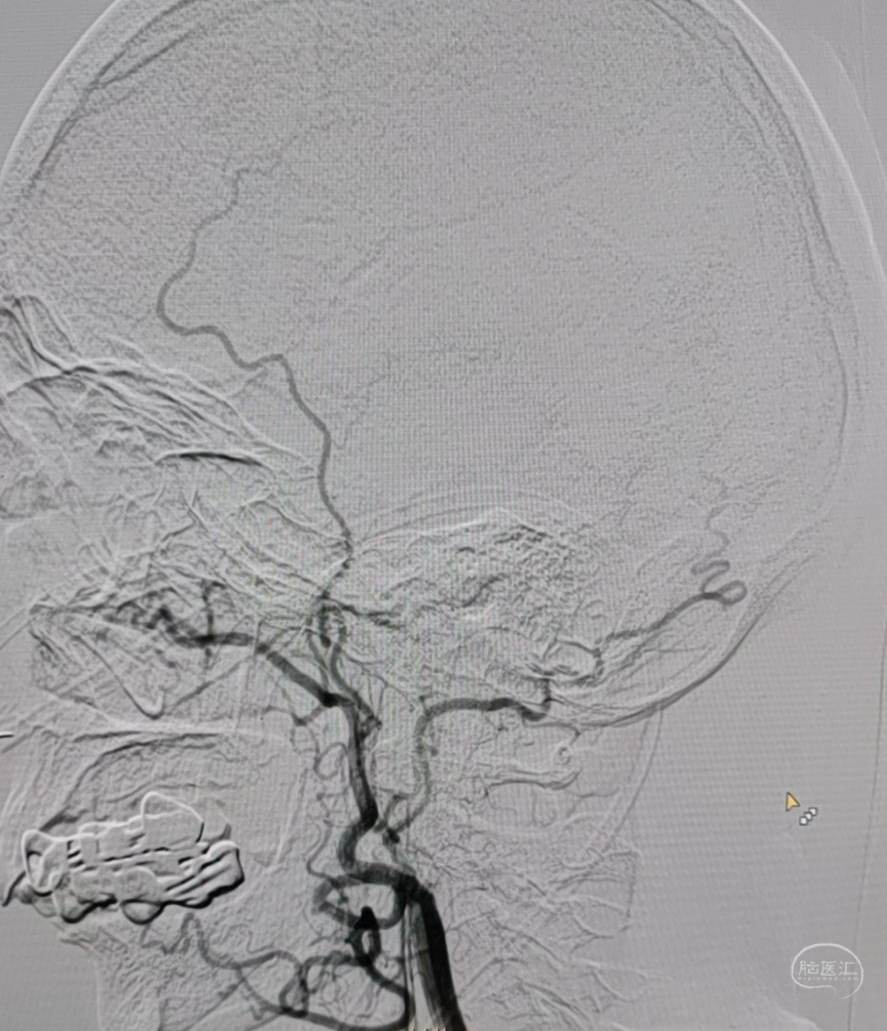

DSA:左侧颈内动脉闭塞。

颞浅动脉未向颅内代偿。

DSA:右侧大脑中动脉、大脑前动脉闭塞,烟雾样血管形成。

颞浅动脉未向颅内代偿。

DSA:左侧大脑中动脉、大脑前动脉闭塞,烟雾样血管形成。

颞浅动脉未向颅内代偿。

DSA:右侧大脑中动脉、大脑前动脉闭塞,烟雾样血管形成。

颞浅动脉未向颅内代偿。

DSA:左侧大脑中动脉、大脑前动脉闭塞,烟雾样血管形成。

颞浅动脉未向颅内代偿。